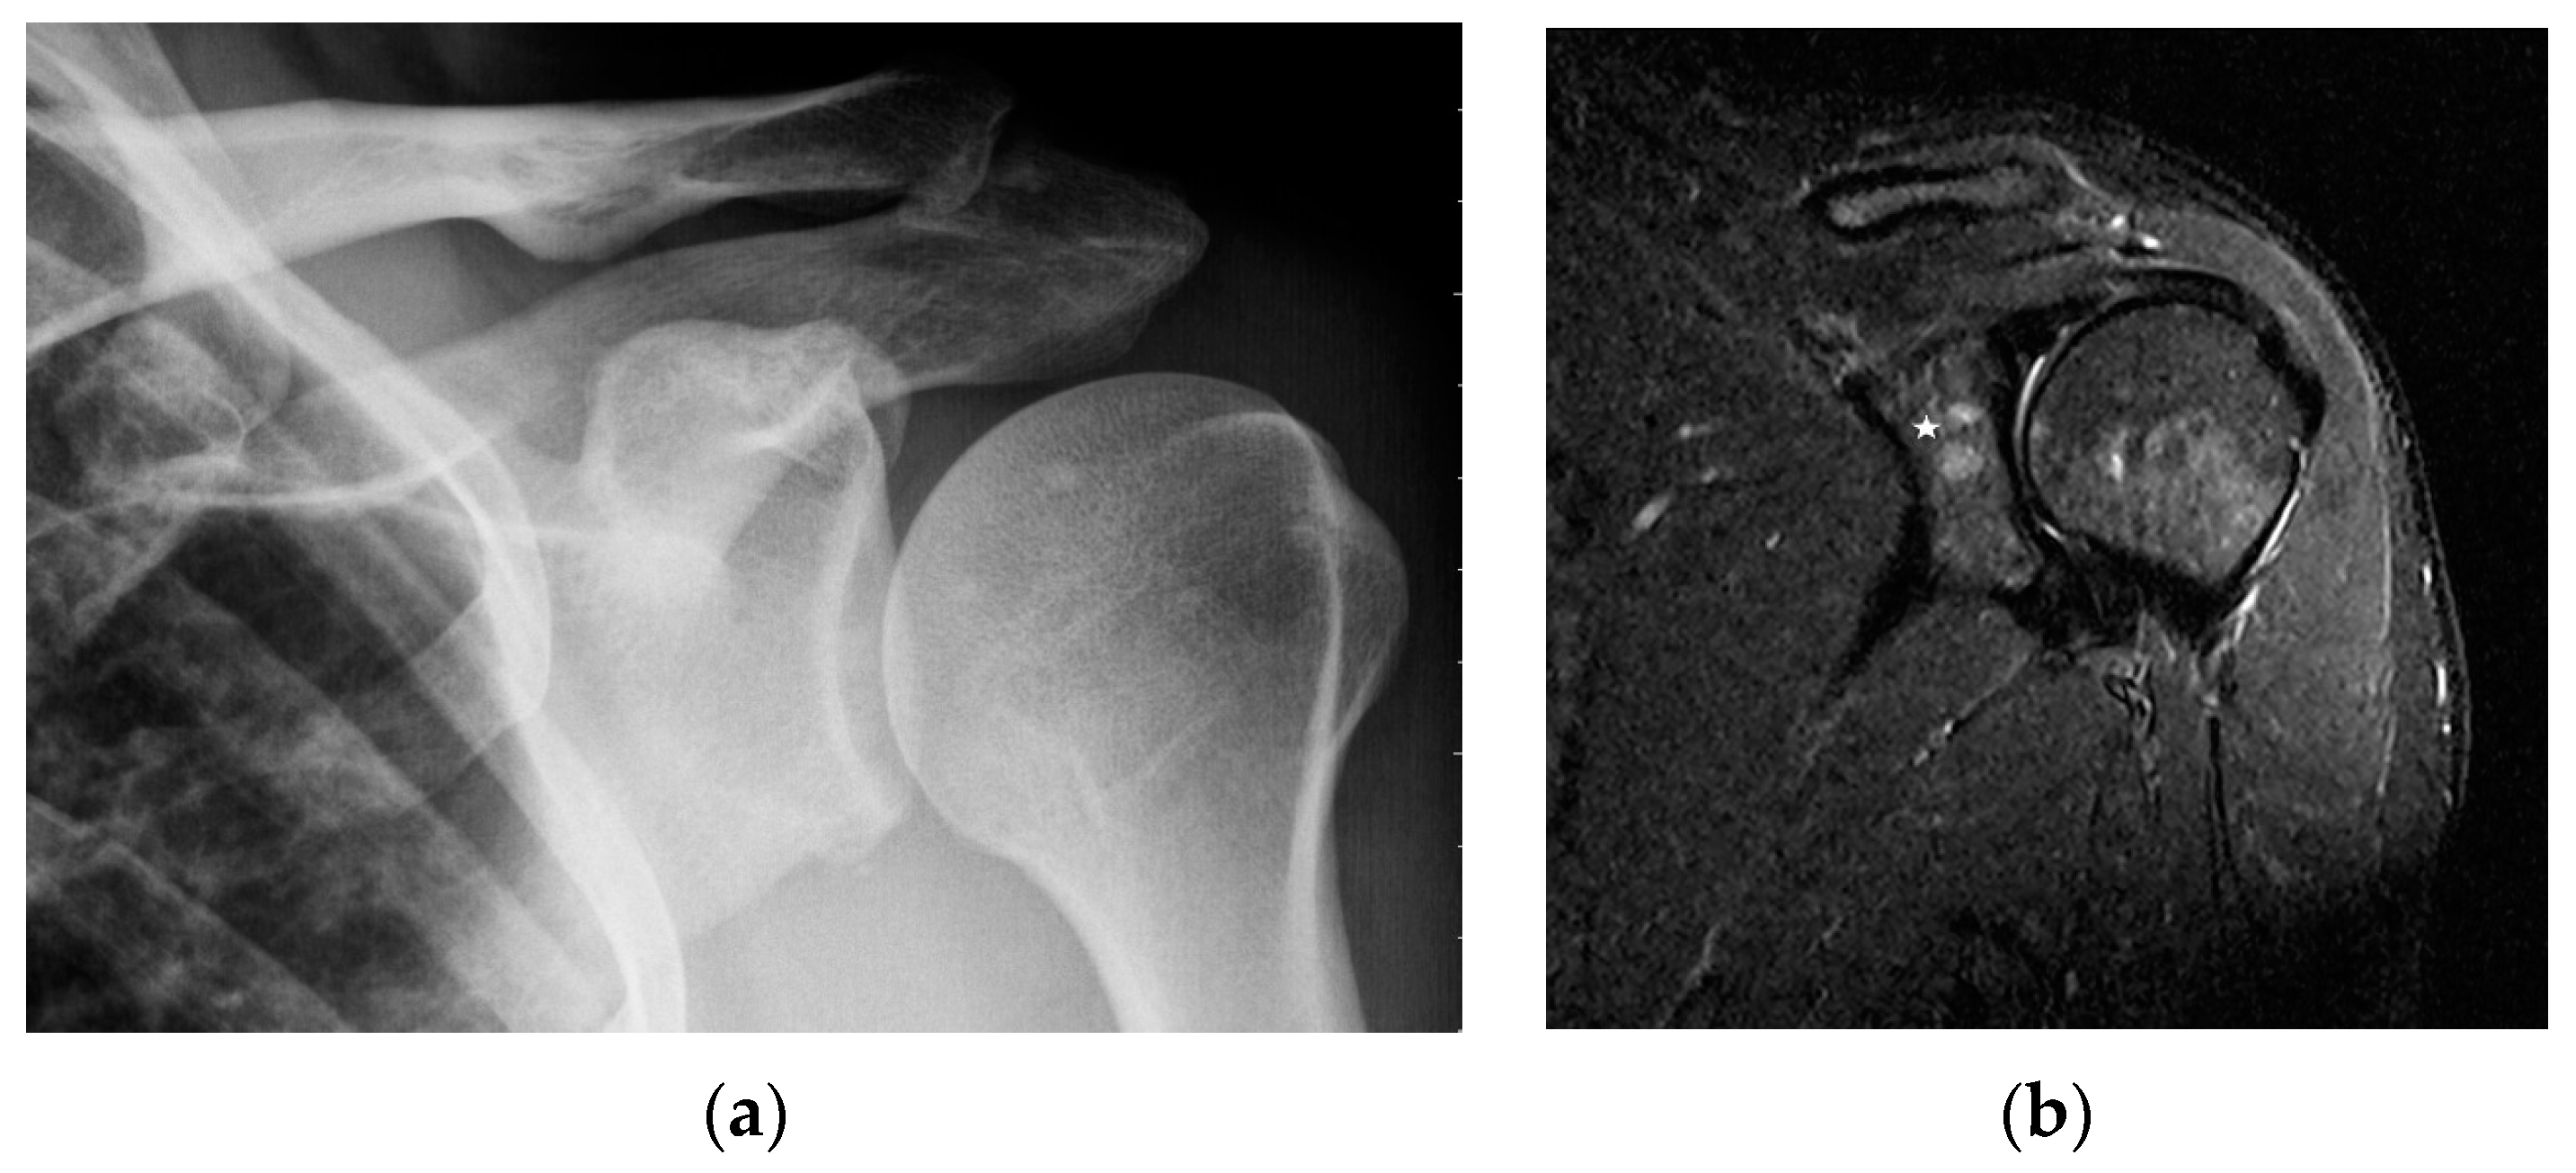

The specificity of MR imaging may be improved by diffusion-weighted imaging (Figure 10). Conte et al. pointed out that the Apparent Diffusion Coefficient (ADC) value of marrow sarcoidosis foci is lower compared to the ADC value of metastases, usually less than 700 µm2/s [21]. This study used DWI/ADC data from the whole-body MRI examination, but it seems that even with examinations limited to a single anatomical region it makes sense to include diffusion-weighted imaging as a part of the protocol. The authors suggest using diffusion images including other routine MR imaging sequences, which may avoid the patient’s administration of contrast. However, this does not change the clinical practice rules, that the suspicious lesion should be verified by histopathological analysis.

Figure 10. MRI of the pelvis, Diffusion-Weighted Imaging (DWI). Multiple bone marrow lesions with restricted diffusion (white arrows).